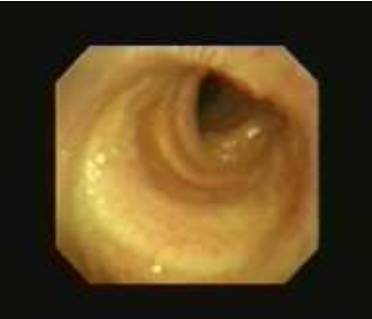

20 下面图中的解剖结构是

A. 成人呼吸道最狭窄的部分

B. 儿童呼吸道最狭窄的部分

C. 成人女性呼吸道最狭窄的部分

D. 成人男性呼吸道最狭窄的部分

20B

环状软骨是儿童呼吸道最窄的一部分而声门是成人呼吸道最窄的部分。如果对一个儿童进行支气管镜检查,记得会厌和喉通常更前,气管更柔软、容易弯曲,口咽部组织和粘膜更柔软易损伤,这些是很重要的 如果必须插管,无接头的气管插管应该用在8岁以下的儿童。气管插管外径应该近似于儿童鼻孔的大小。多数的急诊室均具有Broeslow卷尺更好的测量。